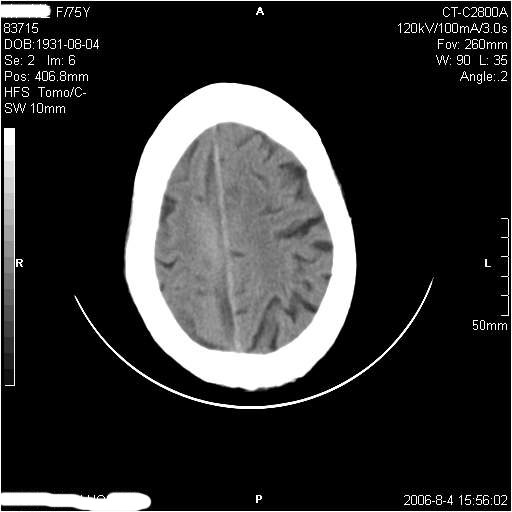

左侧偏瘫3天.

1纵裂硬膜下血肿,2双基底节脑软化灶.

1、纵裂硬膜下血肿,2、右侧室前角旁梗塞;3、双基底节脑软化灶.

有摔倒外伤史,另看右侧灰白质界限.

双侧基底节区多发性腔梗.引起临床症状的主要原因是右侧侧脑室旁的梗塞病灶.

1、该患者从脑实质表现情况看应该年龄较大了,双侧基底节区多发斑片状低密度灶,侧脑室旁白质密度减低,各脑室腔扩大,脑沟裂增宽加深,以上改变符合:皮层下动脉硬化性脑病。

2、上纵裂右侧梭形条状高密度影阴,边缘模糊,周围水肿带环绕,右侧脑室受压变形,有摔倒外伤史,多考虑:纵裂硬膜下血肿。